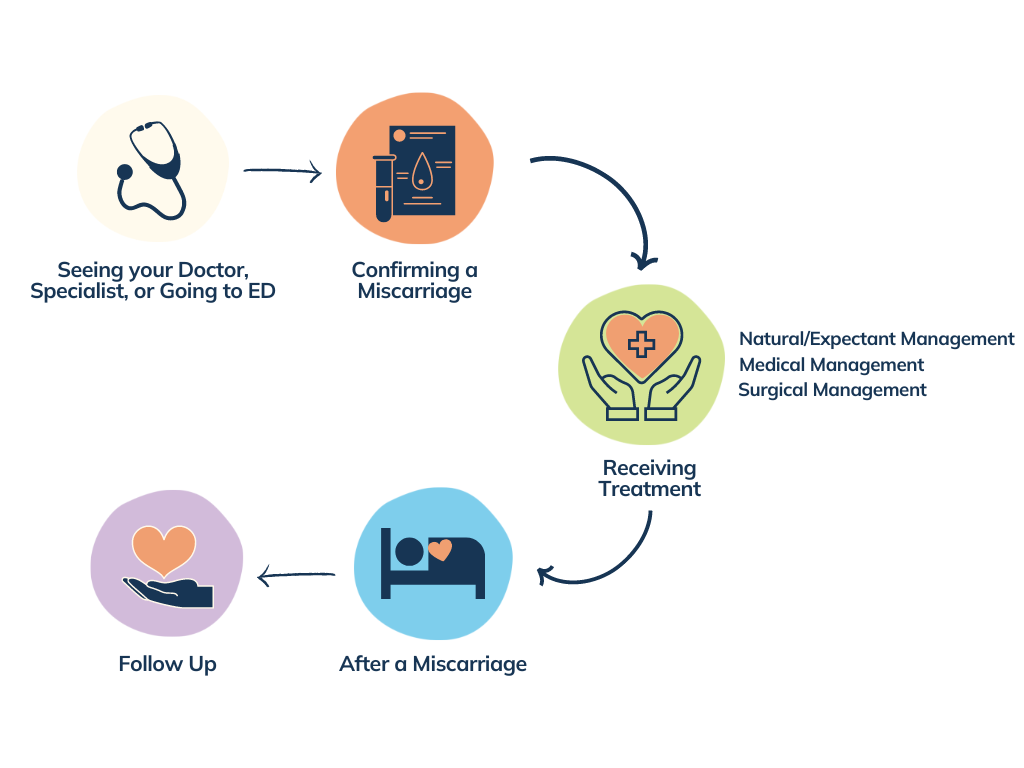

How to tell if you’re having a miscarriage. A lab can examine the tissue to check for signs of a miscarriage. When a miscarriage is confirmed, you'll need to talk to your doctor or midwife about the options.

Miscarriage is commonly diagnosed using a combination of tests, the most standard of which include the hcg blood test, an ultrasound, fetal heart scanning, and a. Passing tissue or blood clots from the vagina. You can practice diaphragmatic breathing at any point after a pregnancy loss, and you don’t even have to get out of bed to do it effectively.